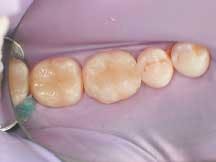

A male patient presented with failing 15-year-old amalgam restorations on Teeth Nos. 17 through 19 (Figure 1) and cold sensitivity on Tooth No. 19. Teeth Nos. 17 and 18 required Class I restorations, while Tooth No. 19 required a Class II restoration. Direct composite resin restorations (4 Seasons Universal Composite and 4 Seasons Flow) were deemed the more appropriate treatment for this patient. This was confirmed following removal of the amalgam restorations, which showed the shallowness of the cavities.

1